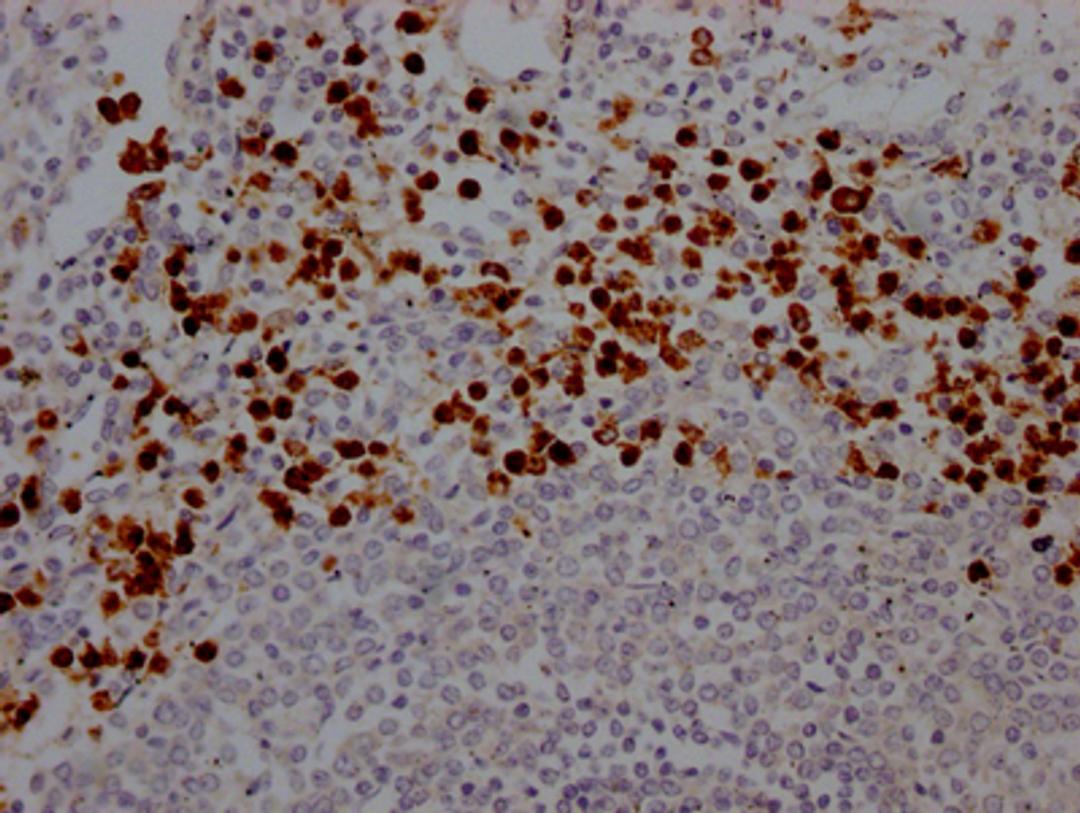

IHC image of CSB-RA617176A0HU diluted at 1:100 and staining in paraffin-embedded human spleen tissue performed on a Leica BondTM system. After dewaxing and hydration, antigen retrieval was mediated by high pressure in a citrate buffer (pH 6.0). Section was blocked with 10% normal goat serum 30min at RT. Then primary antibody (1% BSA) was incubated at 4℃ overnight. The primary is detected by a Goat anti-rabbit IgG polymer labeled by HRP and visualized using 0.05% DAB.